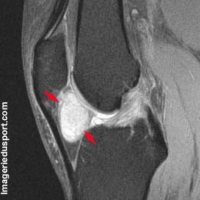

Aspect IRM :

masse ovoïde, bien limitée

typiquement de moins de 4 cm de largeur

parfois polylobée

parfois pédiculée

Signal IRM

- iso ou hyperintense par rapport aux muscles en T1

- signal variable en T2

* hypersignal en T2 fat-sat

* hyposignal sur les séquences T2 fat-sat

- visibilité parfois de zones en asignal témoins de dépôts d'hémosidérines sur les séquences T2 spin echo et sur séquence en écho de gadient

- prise de contraste nette